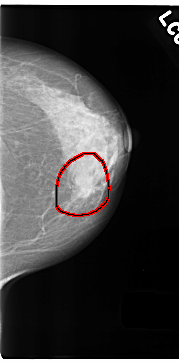

C_0180_1.LEFT_CC

LEFT_CC LINES 4712 PIXELS_PER_LINE 2320 BITS_PER_PIXEL 12 RESOLUTION 50 OVERLAY

FILE: C_0180_1.LEFT_CC.OVERLAY

TOTAL_ABNORMALITIES 1

ABNORMALITY 1

LESION_TYPE MASS SHAPE LOBULATED MARGINS SPICULATED

ASSESSMENT 5

SUBTLETY 5

PATHOLOGY MALIGNANT

TOTAL_OUTLINES 1

BOUNDARY